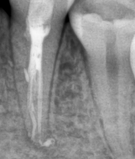

В стоматологической клинике "5 Принципов" в Симферополе мы гордимся тем, что каждый пациент получает индивидуальный подход и безупречный результат в области эндодонтического лечения под микроскопом. Наши специалисты применяют современные цифровые технологии, микропроцессорные и нейромодуляционные инструменты, что позволяет достичь максимальной точности и минимального дискомфорта. В портфолио клиники — широкий спектр кейсов: от первичной диагностики пульпита до сложной ретенированной резорбции и повторной эндодонтии. Мы беремся за зубы любых степеней сложности: от моляра до резцов, используя щадящие концевые инструменты и безболезненные методы постоянной анестезии. Все процедуры проходят под увеличением, что обеспечивает точное удаление инфицированной ткани и сохранение естественной анатомии зуба.Особое внимание мы уделяем постпроцедурному наблюдению: контроль за герметичностью заполнения корневых каналов, профилактические рекомендации и возможная корректировка плана лечения при необходимости. В "5 Принципах" мы разумно сочетаем комфорт, эстетическую привлекательность и долгосрочную функциональность. Результат — здоровые зубы, уверенная улыбка и спокойствие наших пациентов в Симферополе. Запишитесь на консультацию и убедитесь сами в нашем подходе к качественному эндодонтическому лечению.